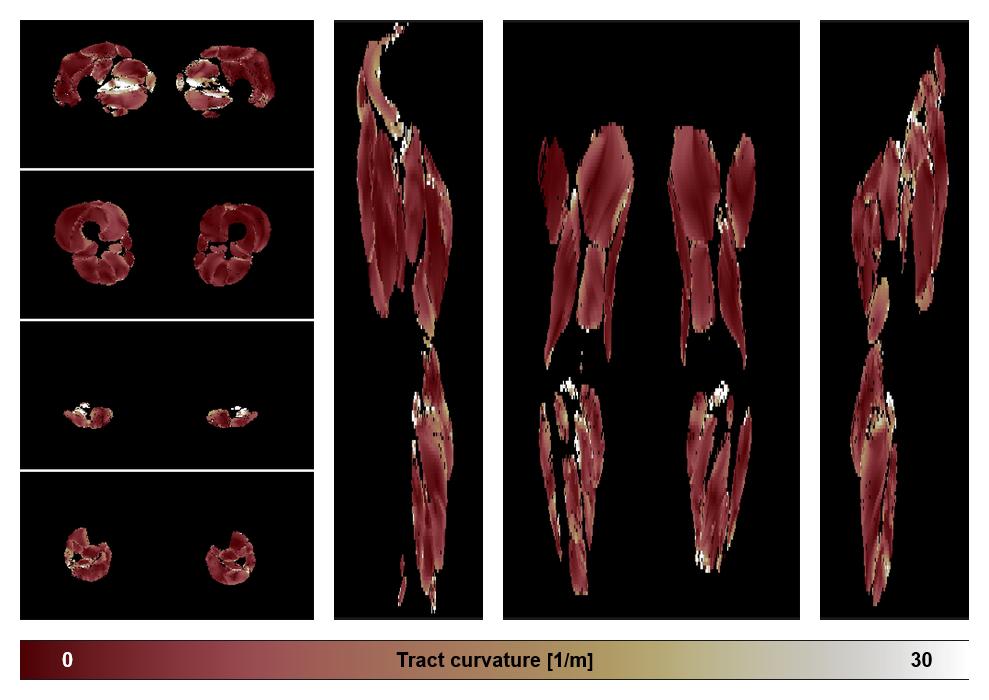

• Muscle fiber curvature map

Muscle fiber tract curvature map based on whole leg DTI based fiber tractography.